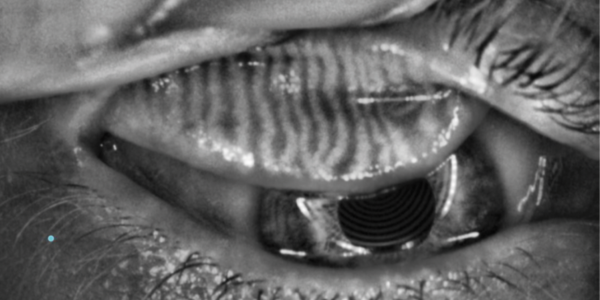

Basándose en la información paquimétrica y de elevación, el VX210 permite a los profesionales visualizar y analizar la posición de los anillos intraestromales, que son útiles para corregir ciertas formas de queratocono y errores refractivos.